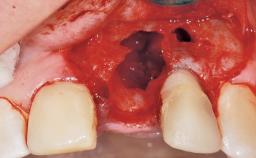

Bone Augmentation Horizontal|Staged

Augmentation Materials Xenogenous|Membrane

Bone Volume Horizontally and vertically sufficient Horizontally deficient Deficient vertically or deficient vertically AND horizontally

Bone Volume Deficient horizontally, requiring prior grafting